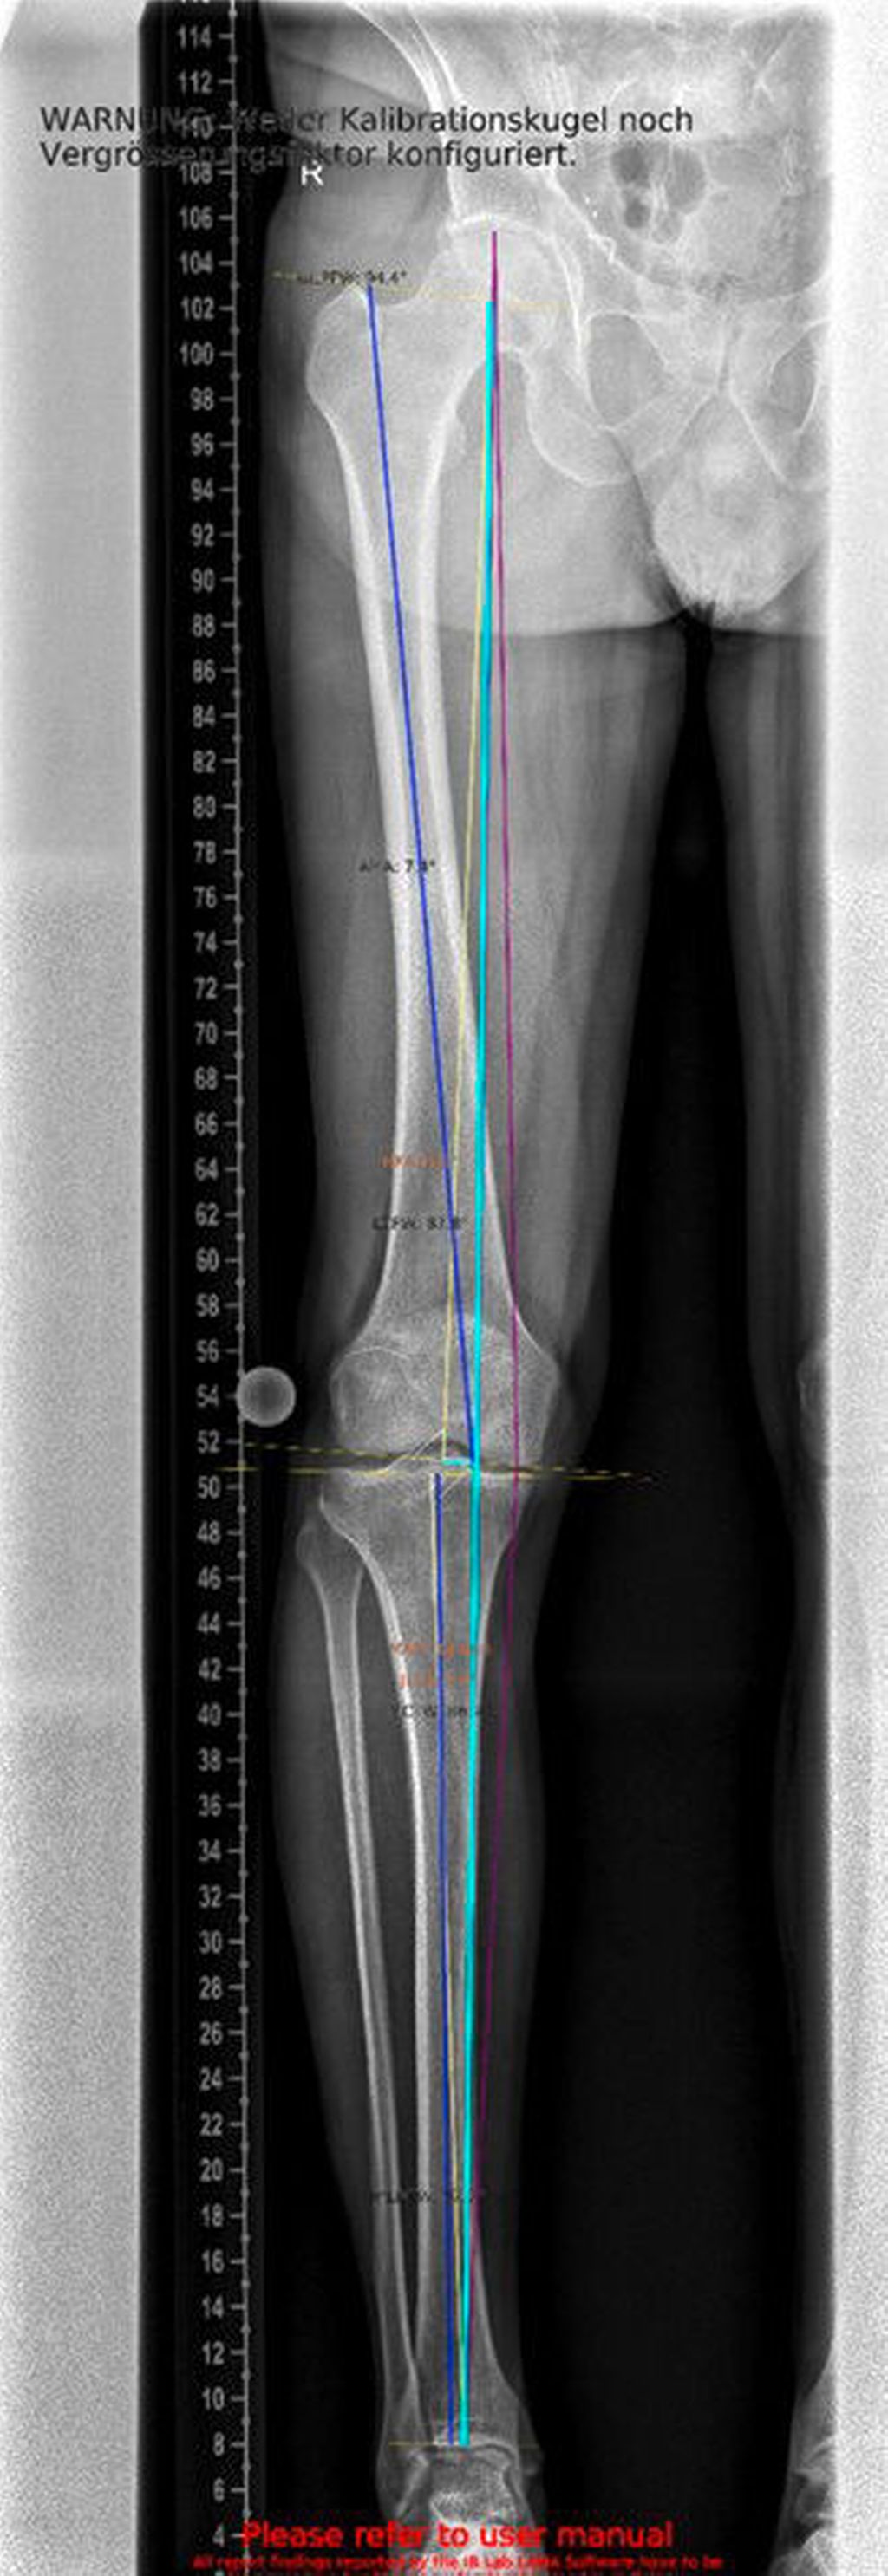

Ein 62-jähriger Patient stellte sich im März 2025 mit belastungsabhängigen Knieschmerzen rechts vor. Im MRT zeigte sich eine Läsion des medialen Meniskus, sodass in Zusammenschau mit dem positiven Meniskuszeichen in der klinischen Untersuchung eine partielle Meniskektomie durchgeführt wurde. Die postoperative Phase verlief zunächst unauffällig. Der Patient berichtete über ein beschwerdefreies Intervall von rund sieben Wochen. Anschließend entwickelten sich jedoch erneut zunehmende Schmerzen im rechten Kniegelenk, die eine erneute Vorstellung in der Spezialambulanz erforderlich machten. Er berichtete vor allem über belastungsabhängige Schmerzen im Bereich des medialen Kniegelenks. Daraufhin wurde ein Ganzbeinröntgen zur Beurteilung der Beinachse durchgeführt, hier zeigte sich eine varische Beinachse mit 5 Grad Varus (Abb.1). In der ergänzend durchgeführten MRT-Untersuchung konnte medialseitig eine ausgeprägte Nekrosezone am medialen Femurkondyl nachgewiesen werden (Abb.2). Schlussendlich wurde aufgrund dieses Befundes die Indikation zur Implantation einer medialen Hemischlittenprothese rechts gestellt, die schließlich im August 2025 komplikationslos durchgeführt wurde (Abb.3+4).

Ein weiterer kritischer Aspekt ist das Risiko für eine postarthroskopische Osteonekrose. Hinsichtlich der Pathogenese werden unterschiedliche Ursachen diskutiert: Zum einen gelten Meniskusläsionen als möglicher Hauptfaktor, zum anderen werden intraoperative Traumata, ein erhöhter intraartikulärer Druckanstieg während der Arthroskopie sowie veränderte Lastübertragungen nach partiellen Meniskusresektionen als ursächlich in Betracht gezogen.17 Nach partiellen Meniskusresektionen kann es zu einem signifikanten Anstieg subchondraler Druckspitzen kommen. Diese mechanische Überlastung fördert die Entstehung von Mikrofrakturen sowie subchondralen Perfusionsstörungen, die in der Folge in eine Osteonekrose übergehen können. Kobayashi et al. berichteten, dass bei 25% der Patient:innen nach partieller Meniskektomie eine juxtaartikuläre Osteonekrose auftrat, nach totaler Meniskektomie sogar bei 50%. Die Lokalisation der Nekrosen war variabel: In 16 von 32 Fällen manifestierten sie sich sowohl am tibialen als auch am femoralen Kondylus, in zehn Fällen isoliert am Tibiaplateau und in sechs Fällen ausschließlich am Femurkondylus. Nach medialer Teilmeniskektomie zeigte sich eine Prädisposition zur Manifestation im medialen femoralen Anteil, wohingegen nach lateraler Teilmeniskektomie überwiegend der laterale tibiale Anteil betroffen war.18 In der klinischen Praxis bedeutet dies, dass präoperativ eine alleinige MRT-Untersuchung des Meniskus nicht ausreicht. Vor allem bei klinischem Verdacht auf eine Achsenabweichung sollte eine Ganzbein-Standaufnahme zusätzlich durchgeführt werden. Nur so lässt sich die mechanische Beinachse zuverlässig beurteilen und in die Therapieplanung einbeziehen.